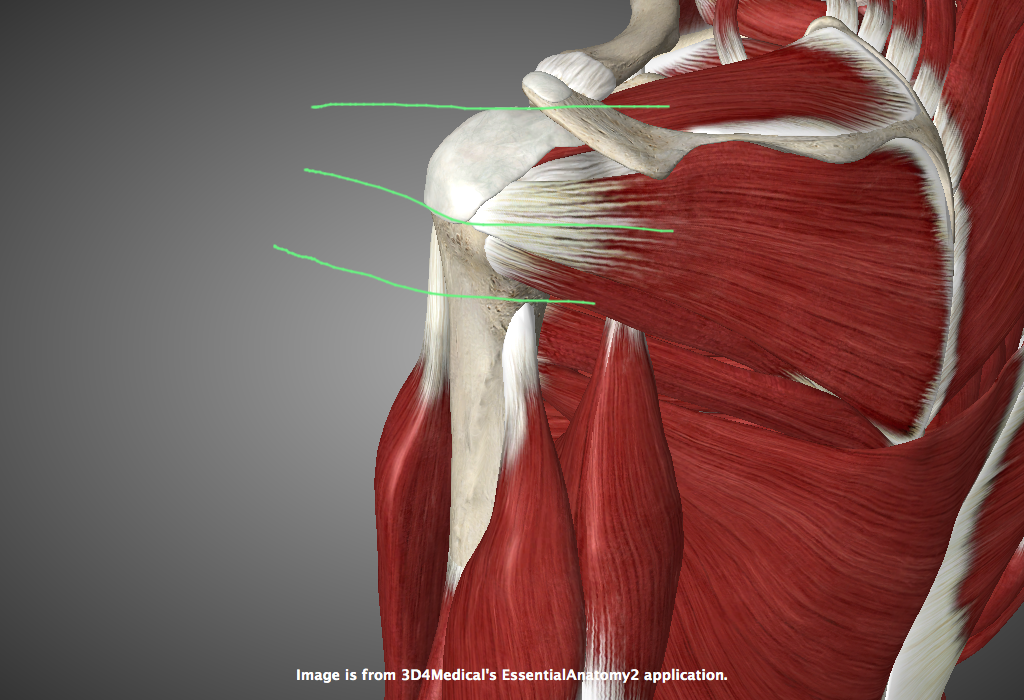

Фотографии поддельтовидной мышцы плечевого сустава